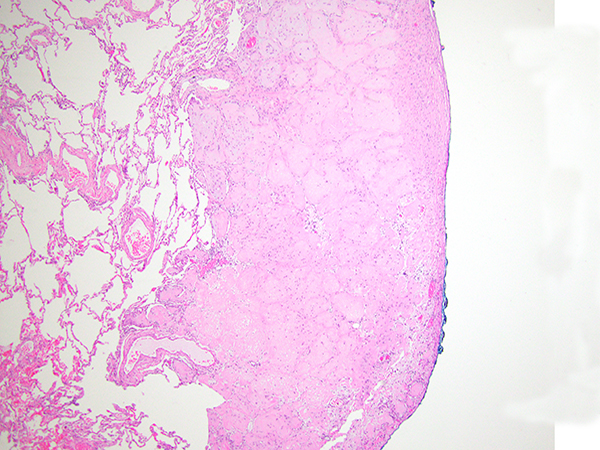

The wedge biopsy of the right middle lobe showed multiple circumscribed nodules composed of bland epithelioid cells with abundant eosinophilic cytoplasm, protruding into the alveolar spaces with no disruption of the architecture and lack of reactivity of the pneumocytes (Figures 2-5). The nodules appeared hyalinized with cellular accentuation in the periphery and focally myxoid stroma. The neoplastic cells showed intracytoplasmic lumina/vacuoles and occasional nuclear inclusions. By immunohistochemistry, the neoplastic cells expressed multiple vascular markers including CD34, CD31, ERG and Fli1, as well as focal expression of low-weight cytokeratins and EMA. Negative stains included TTF-1, p40, Pax8, and CK7. No amyloid was noted on Congo red stain. There was no evidence of granulomatous inflammation.

The histologic features as mentioned above, together with the clinical history, are very characteristic of epithelioid hemangioendothelioma (EHE). This neoplasm is regarded to as a “borderline” neoplasm, with some authors considering it a low-grade sarcoma. Pulmonary EHE occurs predominantly in young to middle age females and it is most often asymptomatic. As mentioned above, radiologically EHE presents as multiple and bilateral small nodules diffusely affecting the lungs and, therefore, is often confused with lung metastasis, particularly leiomyomas and lymphomas. The histologic features are as mentioned above, with the very characteristic neoplastic epithelioid cells with abundant eosinophilic cytoplasm and the presence of cytoplasmic vacuoles/lumina often containing red blood cells (so-called “blister” cells) and hyalinized to myxoid stroma. EHE can also extensively involve the pleural surface. Pathologists should make an effort to recognize clues to the vascular nature of this neoplasm in order to avoid confusing it with granulomatous processes (particularly sarcoidosis) or carcinomas. Figure 5 exemplifies an area of granulomatous appearance in this case, that could easily be confused with a granuloma. Recently, the majority of EHEs have been shown to harbor the t(1,3) translocation resulting in the WWTR1-CAMTA1 fusion gene, which can be tested by cytogenetic techniques or FISH studies.